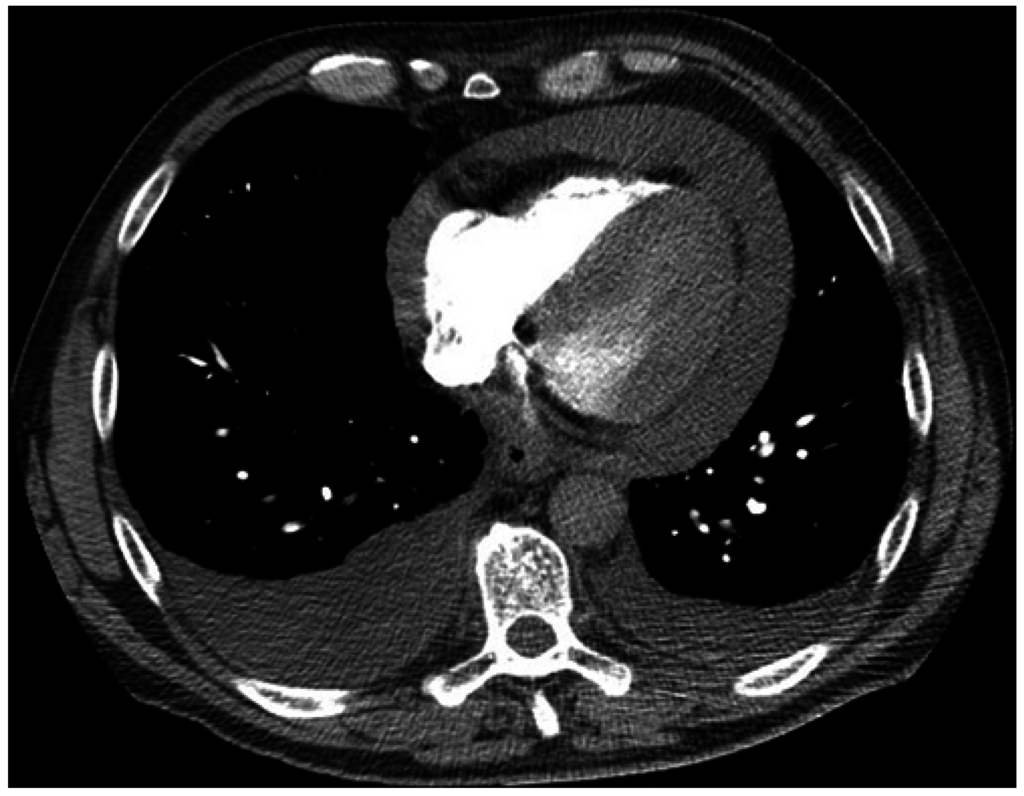

4. Case 3